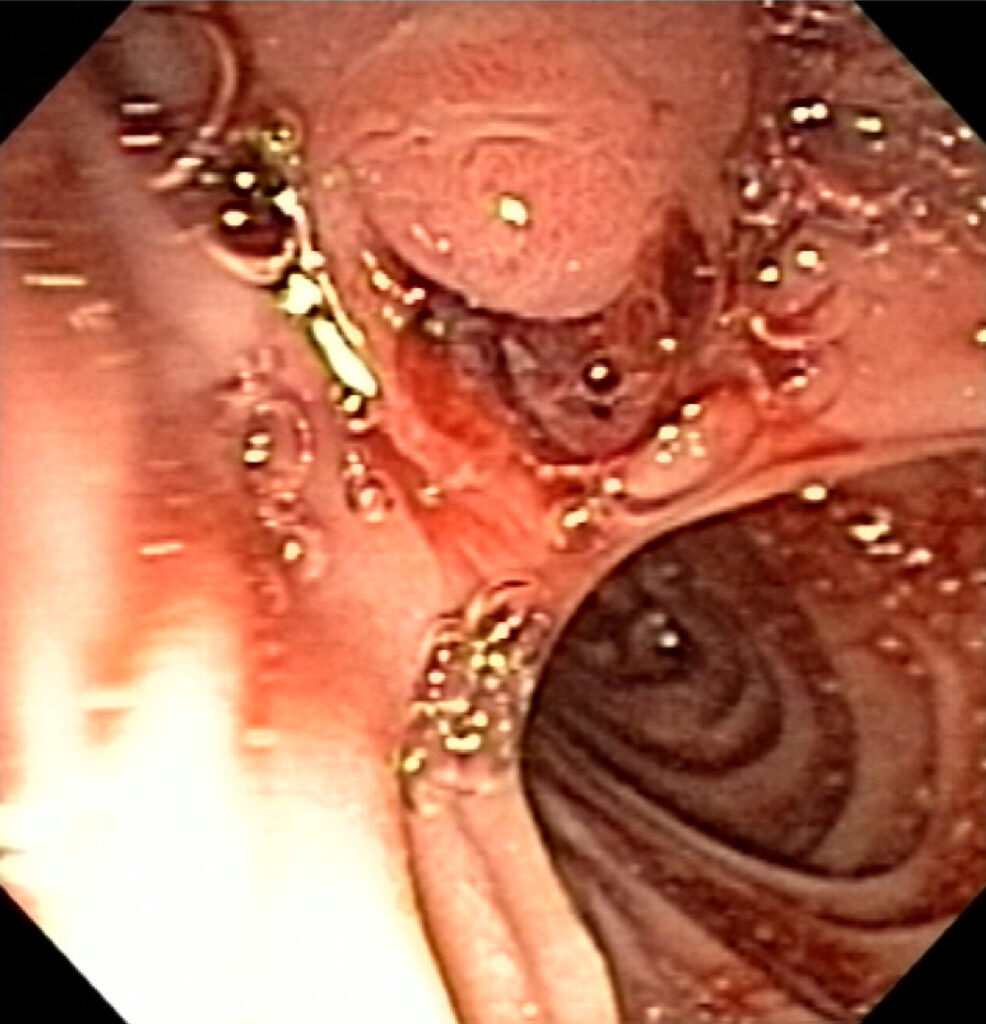

Hemorragia oculta del tubo digestivo

La hemorragia oculta del tubo digestivo se refiere a cualquier sangrado que ocurre en el tracto gastrointestinal sin manifestarse como hemorragia evidente en las heces o el vómito. Es decir,…